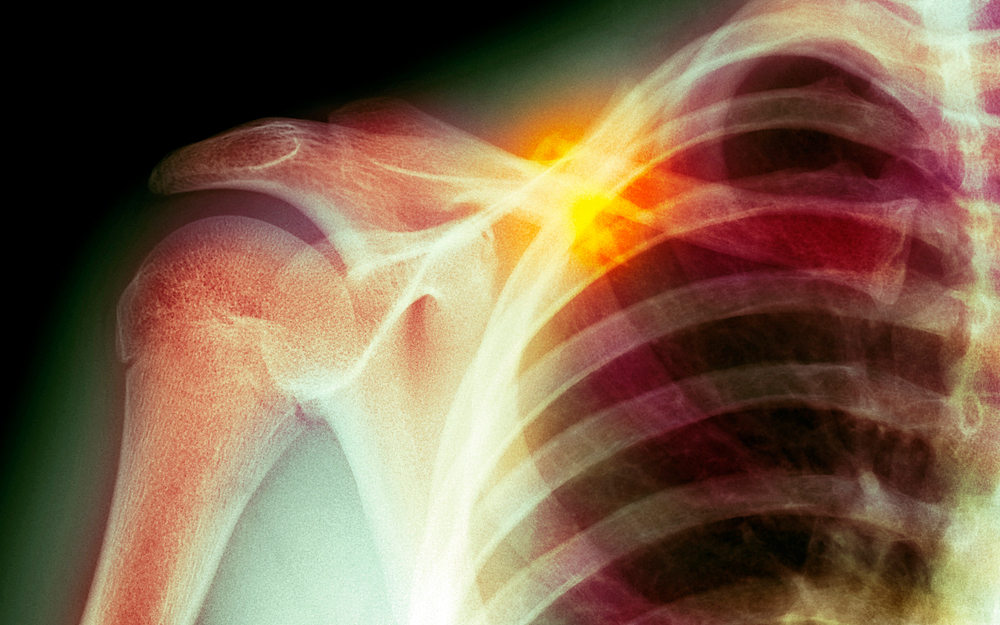

X-ray of a shoulder.